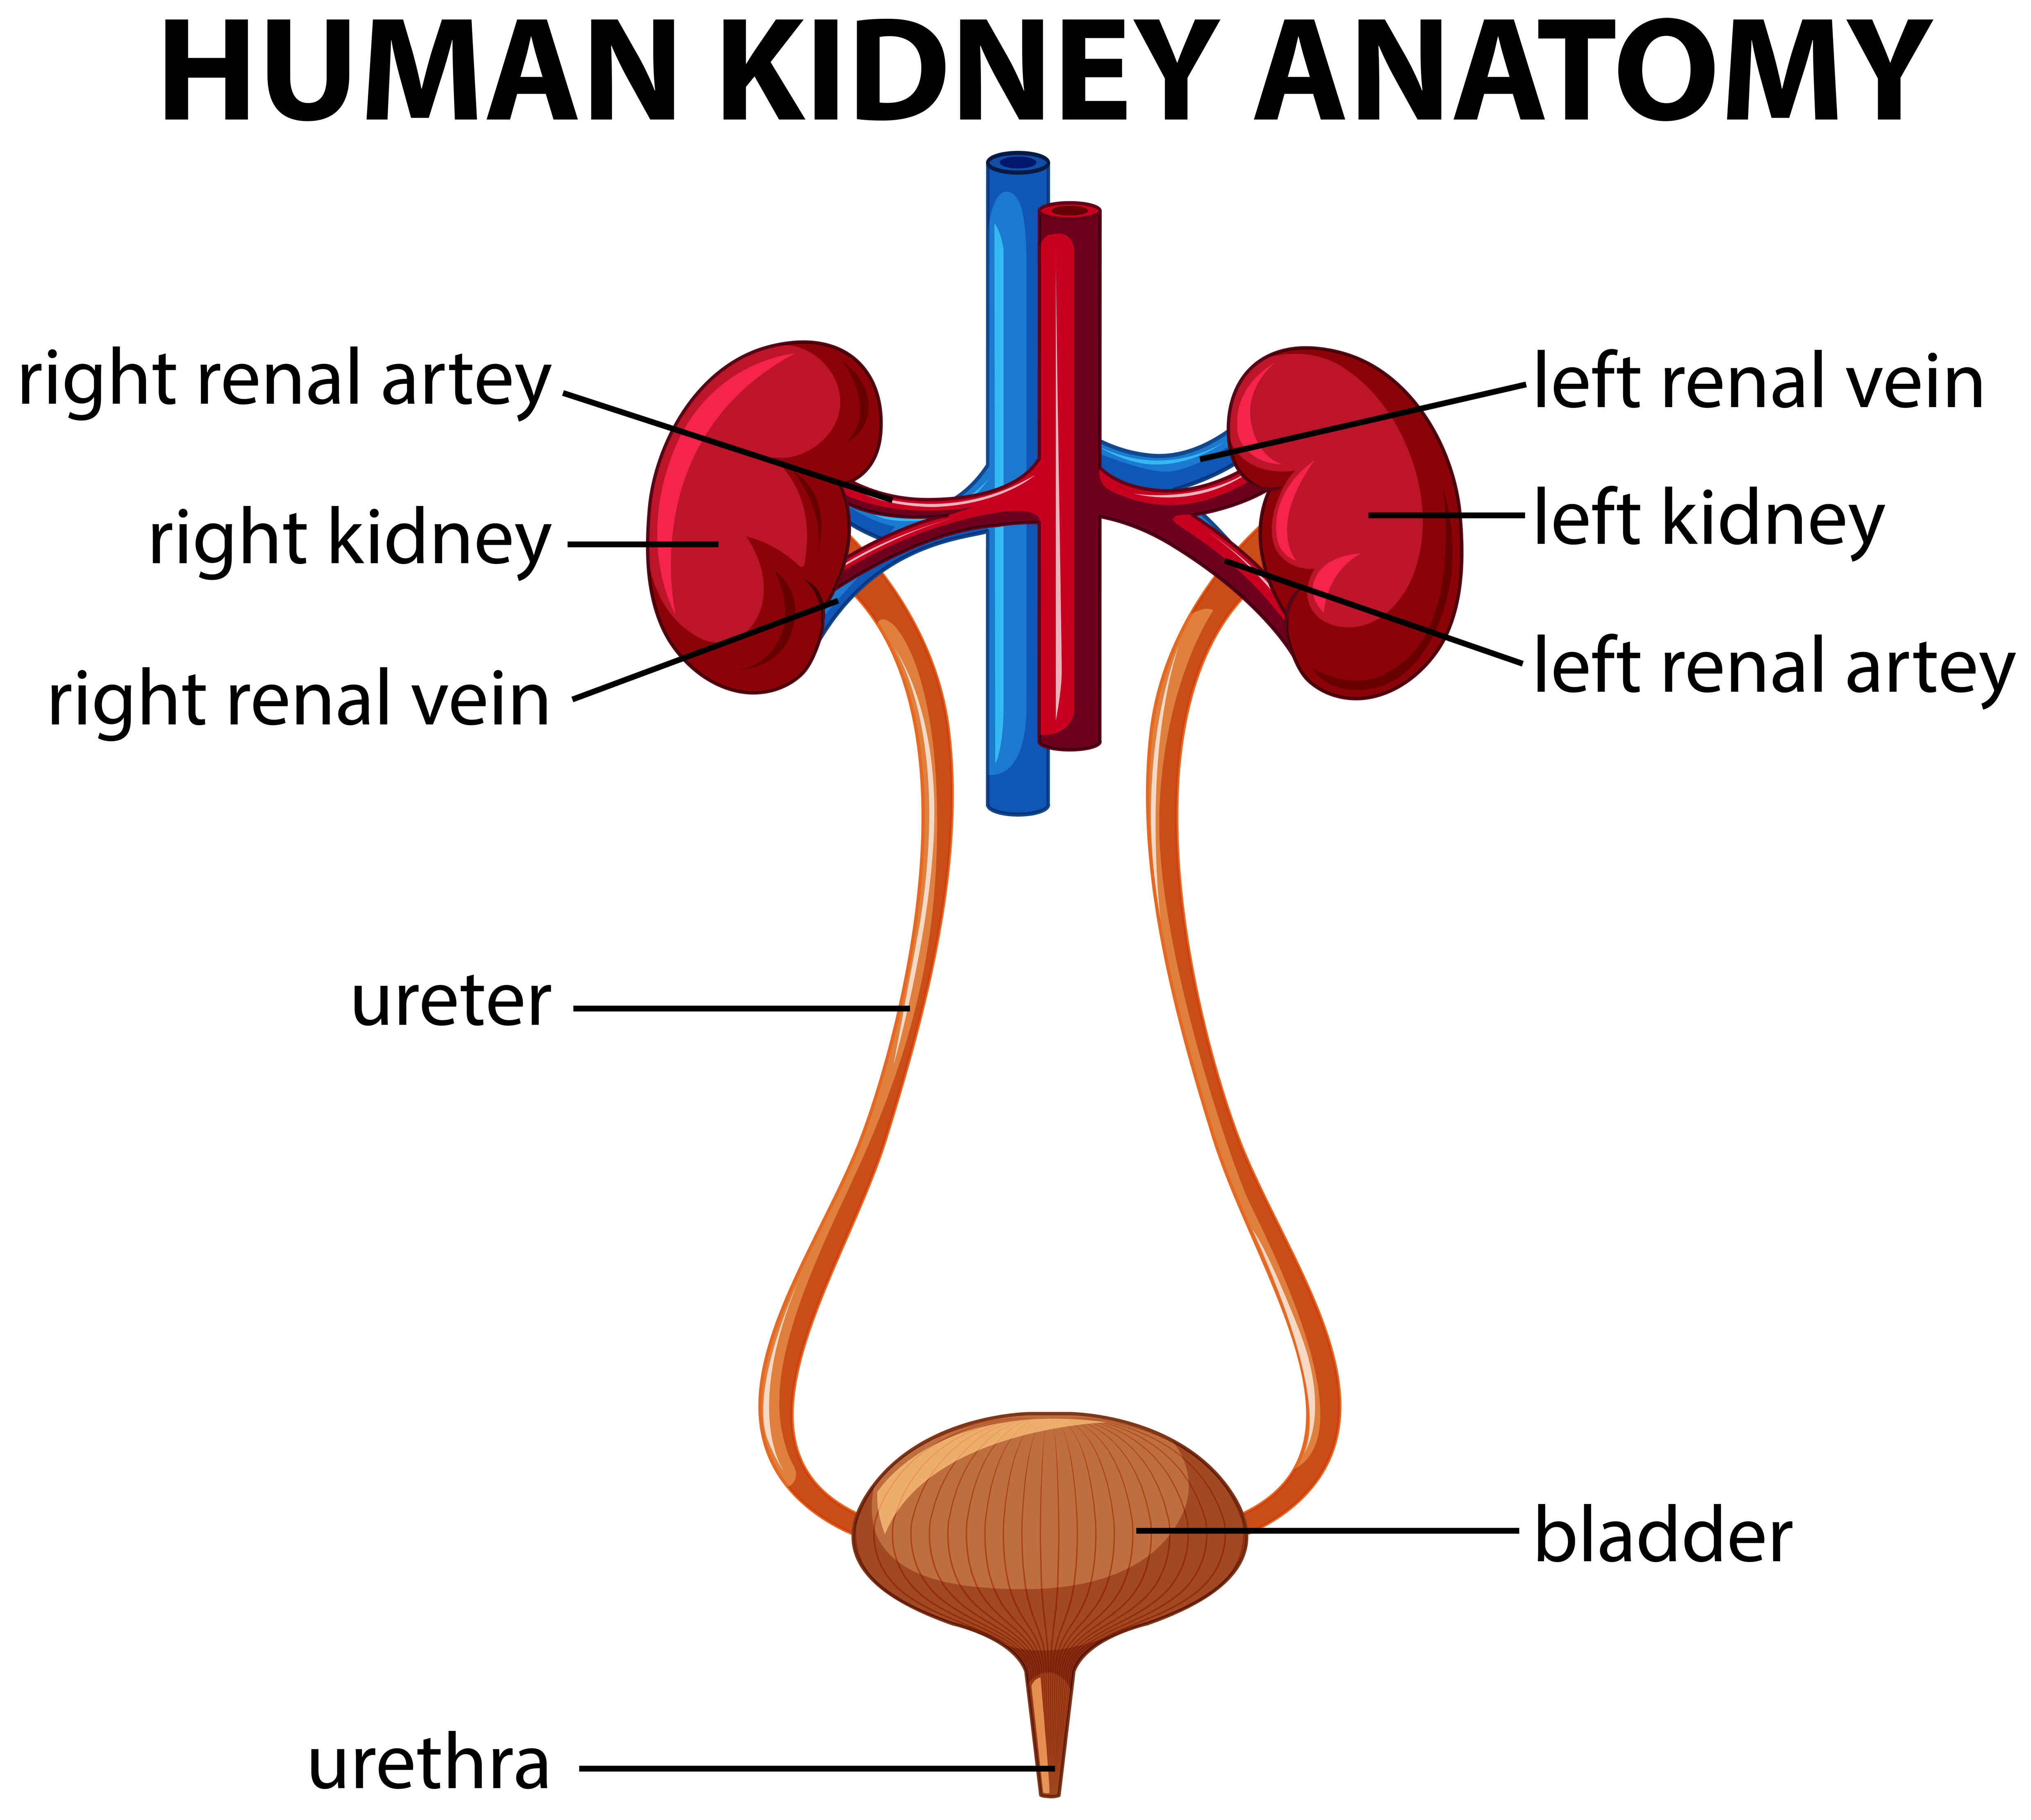

location of the bladder in the human body

Posts: location of the bladder in the human body